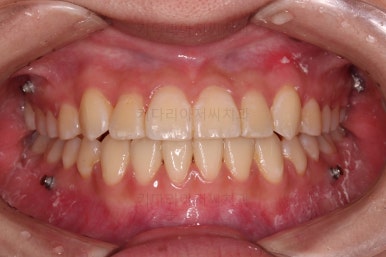

덧니가 완전히 개선디ㅗ었고 필요한 충치치료도 부분적으로 진행했고요.

중앙선이나 교합도 양호하게 마무리 했습니다.

환자분이 원하는 포인트들이 다 개선되었고요.

웃을 때 보이는 느낌도 많이 좋아졌네요.

옆라인도 입이 안나오게 비발치 교정 마무리 잘 되었고요.

묘하게 옆라인의 곡선이 더 예뻐졌죠?

충치도 틀린그림 찾기 수준으로 진짜 필요한 몇 개만 치료를 하고 연산동교정치과 마무리를 했습니다. 어차피 유지관리 체크를 꾸준히 내원하실 거기 때문에 지켜보기로 했습니다.

이상 미니스크류를 이용해 비발치로 덧니 치아를 교정치료한 사례였습니다.